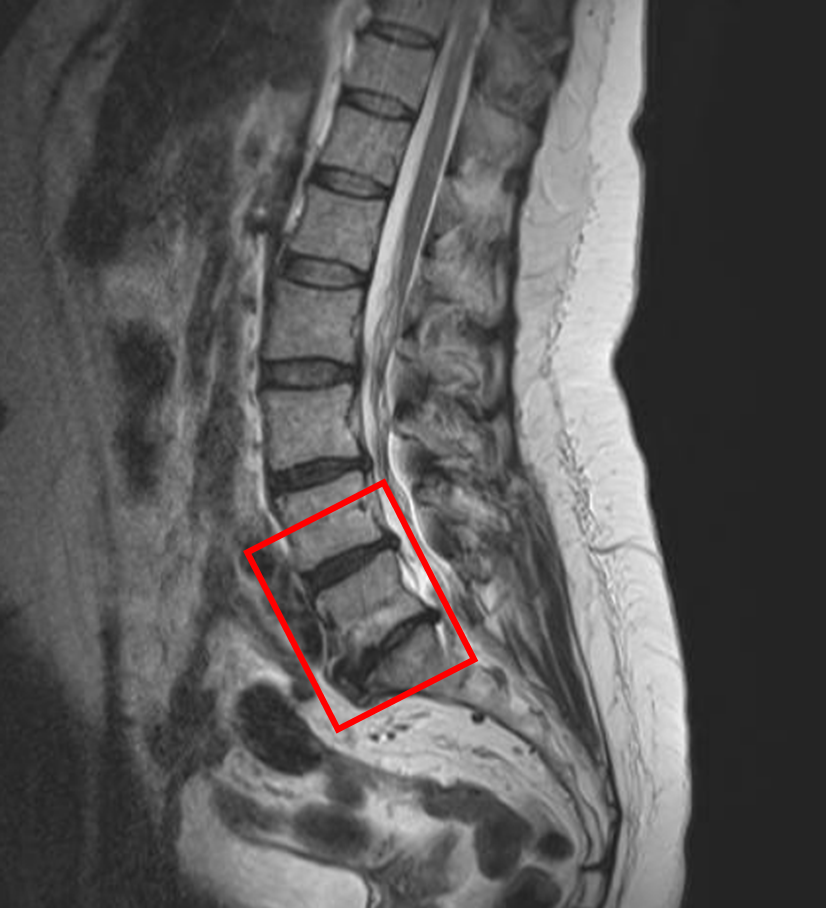

この患者様は赤い枠で示されている箇所(L3/4,4/5)に椎間板変性を認めます。

L5/sは、変性を認めるが症状と結びつかないため適応外となりました。